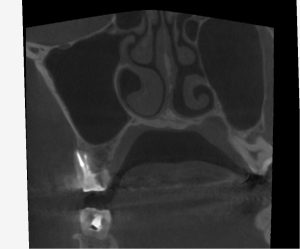

レントゲンを見てみよう。

(術前レントゲン、CT)

全ての根管に、根尖病変が存在する。

打診(+)、咬合痛(+)の状態であった。